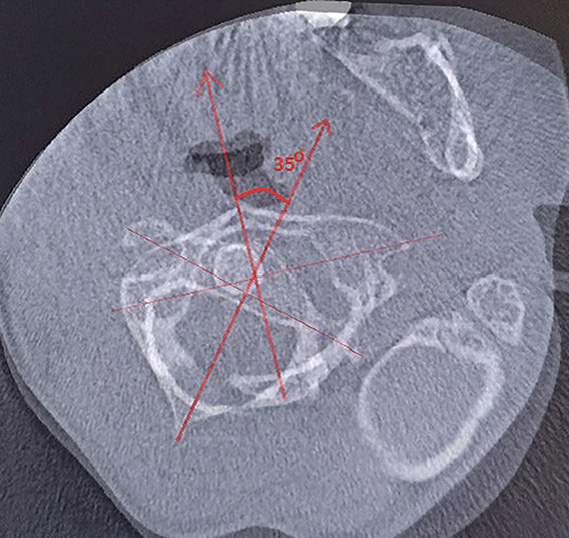

Для уточнения характера выявленных изменений в ручном режиме с помощью программы Adobe Photoshop© выполнено наложение аксиальных срезов 1-го и 2-го шейных позвонков, полученных по отдельности, с созданием единого изображения с возможностью комплексной оценки взаимоотношений изучаемых сегментов (рис. 2). При анализе смоделированного изображения обнаружено, что ротация атланта составляет 35° вправо (рис. 3). Суставные поверхности латерального атлантоаксиального сустава справа совпадают, а слева –суставная поверхность атланта смещена кпереди, что соответствует ротационному подвывиху типа II по классификации J. W. Fielding и R. J. Hawkins [8].

Рис. 3. Наложение изображений А и Б, представленных на рис. 2. Определение угла ротации атланта